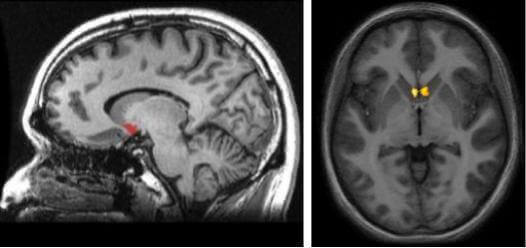

Para entendermos onde está localizada essa estrutura, devemos visualizar a área subcortical (abaixo do córtex) justamente em uma área de interconexão entre o núcleo caudado, o putâmen e o septo. Assim, o aspecto mais interessante sobre o núcleo accumbens e sua localização é o fato de que ele faz parte da via dopaminérgica no cérebro. Esta via é a chamada de via mesolímbica, responsável por nos estimular toda vez que o nosso cérebro entende que estamos realizando experiências positivas e gratificantes.

Cada hemisfério cerebral tem o seu núcleo accumbens. Dessa forma, o sistema de recompensa orquestrado pela dopamina atinge todas as áreas do cérebro. Estamos, por sua vez, diante de uma estrutura que faz parte dos chamados gânglios basais. Assim, embora à primeira vista e através das imagens eles possam parecer bastante pequenos, o que caracteriza o núcleo accumbens é a sua capacidade de conectividade.